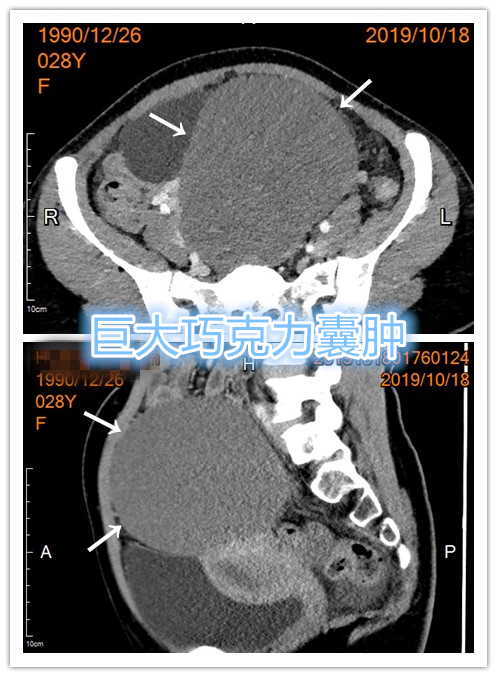

年轻患者,未婚未育,下腹胀半年余,下腹部可见明显隆起包块,行彩超检查提示右侧卵巢巨大巧克力囊肿。经药物保守调理治疗无缓解,因不愿接受妇科手术治疗,就诊要求行介入硬化治疗,遂行CT引导下巧克力囊肿穿刺置管抽吸+硬化治疗。

- CT检查显示巨大巧克力囊肿。

横断位CT

矢状位CT